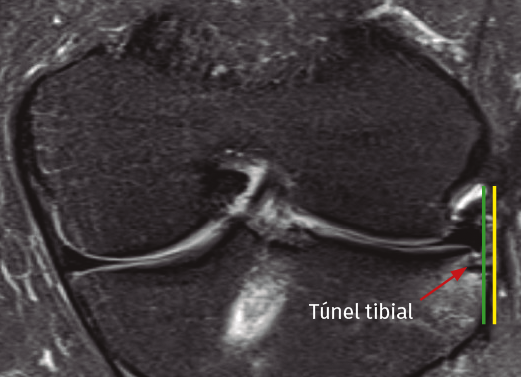

Capsulodesis

Tras la inspección articular, se identifico la cápsula lateral redundante o suelta y se eliminó cualquier osteofito marginal en el borde lateral de la meseta tibial con la ayuda de una fresa motorizada. Seguidamente, se perforaron 2 túneles de 2,5 mm, separados unos 10 a 15 mm, desde la corteza tibial medial, en una dirección oblicua ascendente, terminando en el borde de la meseta lateral, donde la cápsula estaba más desplazada (Figura 1). Este gesto se llevó a cabo con la ayuda de una guía tibial convencional de reconstrucción del ligamento cruzado anterior (LCA) (guía Pinn-ACL®, ConMed-Linvatec, Largo, Florida), evitando cualquier tipo de colisión entre los túneles. A través de los túneles, se pasaron 2 hilos de sutura Vicryl 0 (Ethicon Vicryl®, poliglactina 910 recubierta), que luego servirían para transportar las suturas de la capsulodesis (Figura 2). La cápsula y/o los restos del muro meniscal se capturaron mediante 2 pases sucesivos con puntos simples de PDS n.º 1 (Ethicon PDS II®, polydioxanone, monofilamento), realizados con una técnica de fuera adentro, con ayuda de una aguja espinal del 19 (Figura 3). Estas suturas de transporte fueron sustituidas por suturas de alta resistencia (Hi-Fi® Suture N.º 2, ConMed-Linvatec, Largo, Florida) y se recuperaron a través de cada túnel tibial mediante el hilo previamente pasado (Figura 4). Finalmente, los hilos de alta resistencia se anudaron entre sí sobre la corteza tibial medial, quedando la cápsula firmemente sujeta (capsulodesis) a la meseta tibial lateral (Figura 5).

Figura 1. Imagen artroscópica de la rodilla izquierda a través del portal anteromedial que muestra el túnel tibial de la capsulodesis lateral de 2,4 mm, perforado desde la cara anteromedial de la tibia con la ayuda de una guía tibial de ligamento cruzado anterior (LCA).